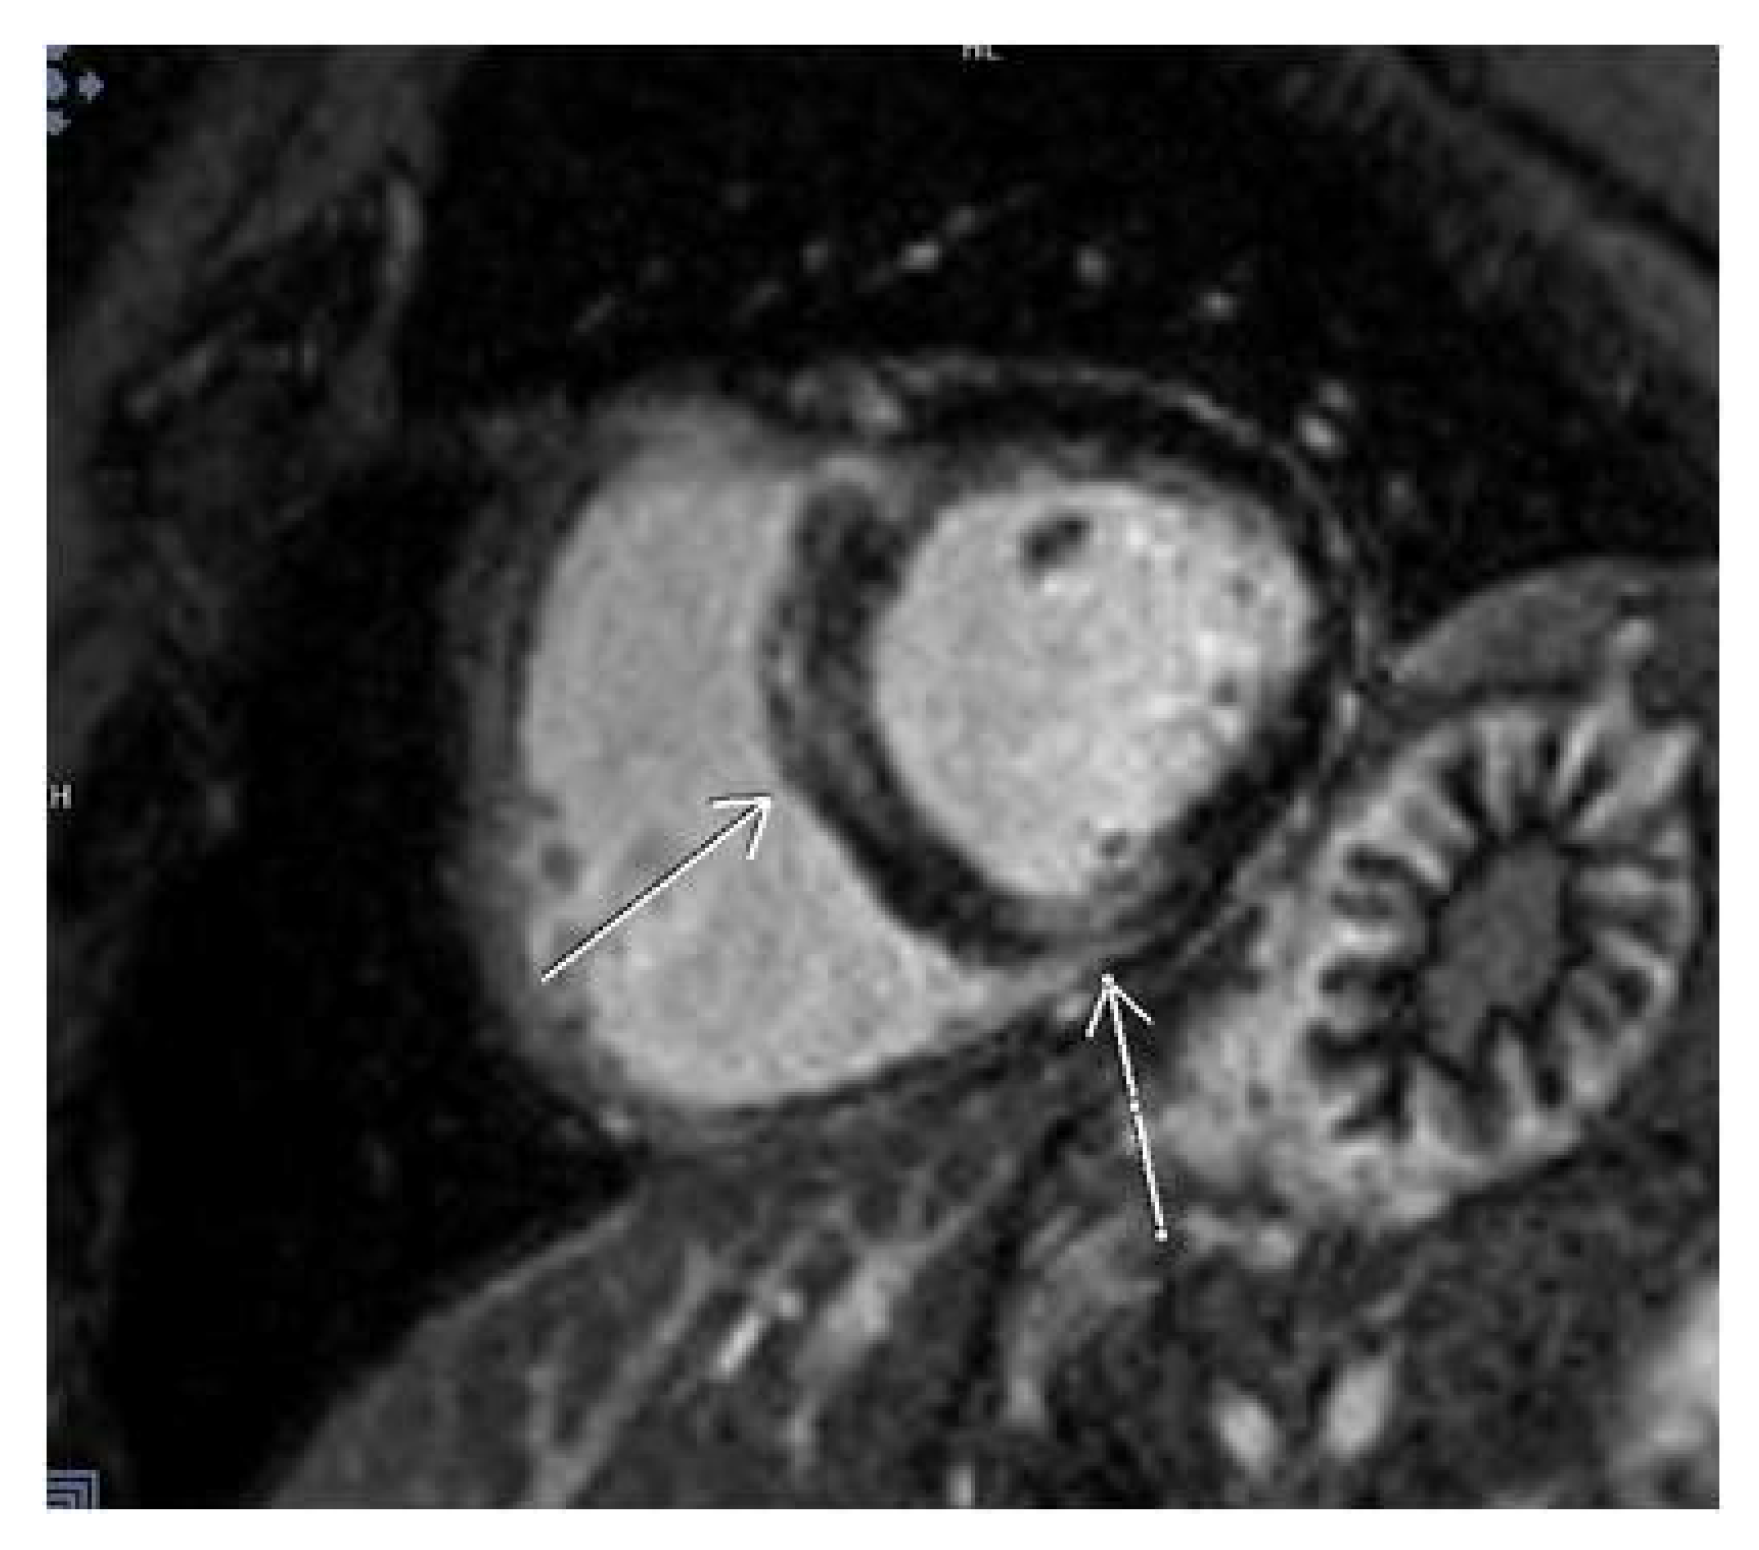

3.2. CMR Findings

3.5. LGE Localization

| Patients with LGE | 54 (38.8%) |

| Lateral | 11 (7.9%) |

| Septal | 9 (6.5%) |

| Multiple segments (more than 3) | 13 (9.4%) |

| Other localizations | 21 (15.1%) |